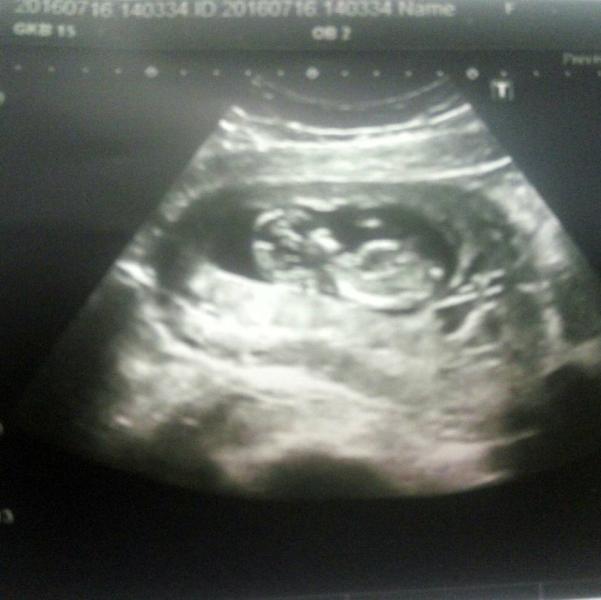

А вот и наше УЗИ со скрининга. К сожалению на фото поместился только один малыш, а рядышком второй домик с еще одним малышом! сейчас они даже лежат одинаково, так что разобрать где первый, а где второй не возможно! лапусики!

@aloraeka У меня двойня, живут в разных домиках и друг дружку трогать не могут. Когда подрастут, наверное будут прятаться друг за дружку, ведь один по передней, а второй по задней стенке прикреплены :)